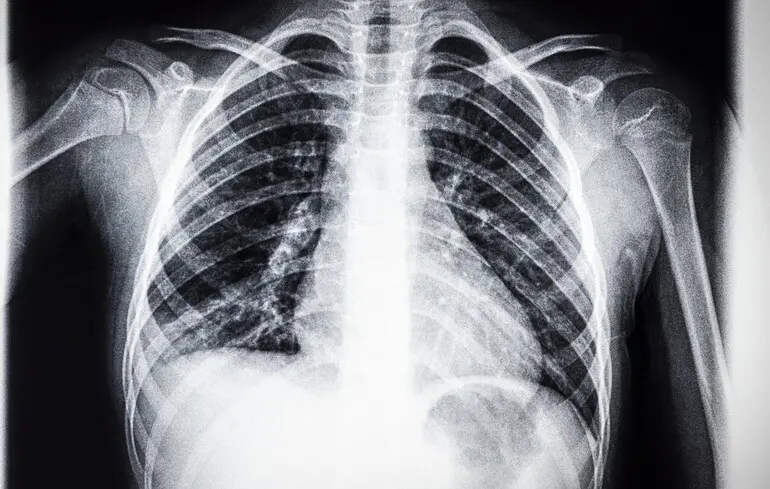

Національне наукове агентство Австралії CSIRO першим у світі розробило програму машинного навчання, щоб спеціалізувати штучний інтелект на читанні рентгену грудної клітини. Натренований у такий спосіб ШІ виявився дуже корисним при діагностиці, повідомляє Medical Xpress.

Для спеціалізації ШІ на читанні рентгенів медичні інженери CSIRO створили базу даних із 46 000 анамнезів реальних пацієнтів, наданих лікарнями США. Також у велику мовну модель завантажили інформацію про всі існуючі стандарти та вимоги до читання радіологічних звітів.

Перевірка на практиці показала, що штучний інтелект на 17% краще ставить діагнози пацієнтам, ніж це робили професійні рентгенологи. Професія зараз переживає у всьому світі нестачу кадрів, тож технологія може вирішити цю проблему і допомогти покращити роботу багатьом медичним закладам.

Це не вперше ШІ використовують для читання рентгенівських знімків. Але австралійська програма дає можливість навчити штучний інтелект повноцінно використовувати анамнез пацієнтів, а не лише плівку.